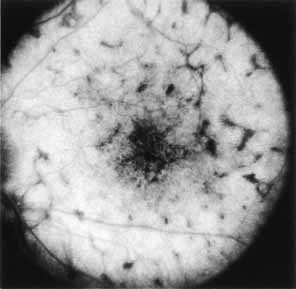

Fluorescein angiography demonstrates increased transmission of choroidal fluorescence in the macula during early phases of the study, without late leakage of dye or fluorescein staining. In addition, an annular pattern of hyperfluorescence is often seen in the macula, highlighting the bull's-eye pattern seen on fundus examination (Fig. 4). Visual field defects include central scotoma, peripheral field loss, and ring scotoma.